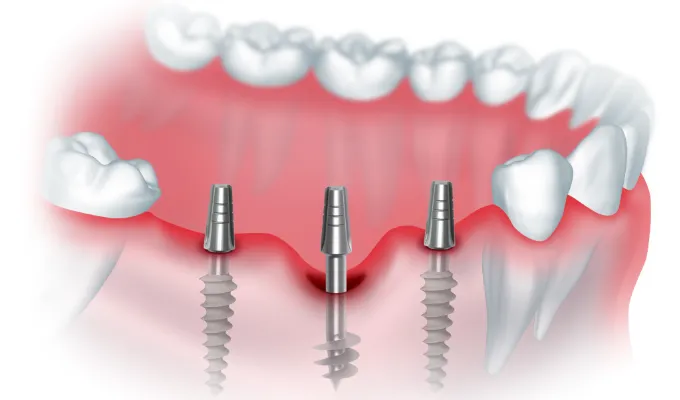

Классические штифты крепятся в губчатом отделе альвеолярного отростка, который быстро рассасывается при потере зубов. Одноэтапная базальная имплантация решает эту проблему: хирурги вживляют удлиненные конструкции в кортикальную пластину и бикортикальные слои.

Эта кость обладает высокой минерализацией, не подвержена воспалениям и не дает усадки с возрастом. Врач устанавливает титановые опоры под углом, минуя гайморовы пазухи и нижнечелюстной нерв.

Гладкое антимикробное покрытие штифтов снижает риск периимплантита при установке в инфицированные ткани. Металлический каркас протеза жестко шинирует опоры сразу после позиционирования, исключая их микроподвижность при жевательных нагрузках.

Протокол немедленной нагрузки требует детального трехмерного планирования. Компьютерная томография позволяет хирургу оценить плотность кости, выбрать длину штифтов и рассчитать точные углы наклона.

Восстановление одного утраченного зуба по этой технологии не проводится. Протокол требует установки от шести до 12 опорных элементов на одну челюсть для создания перекрестной стабилизации и правильного распределения давления.